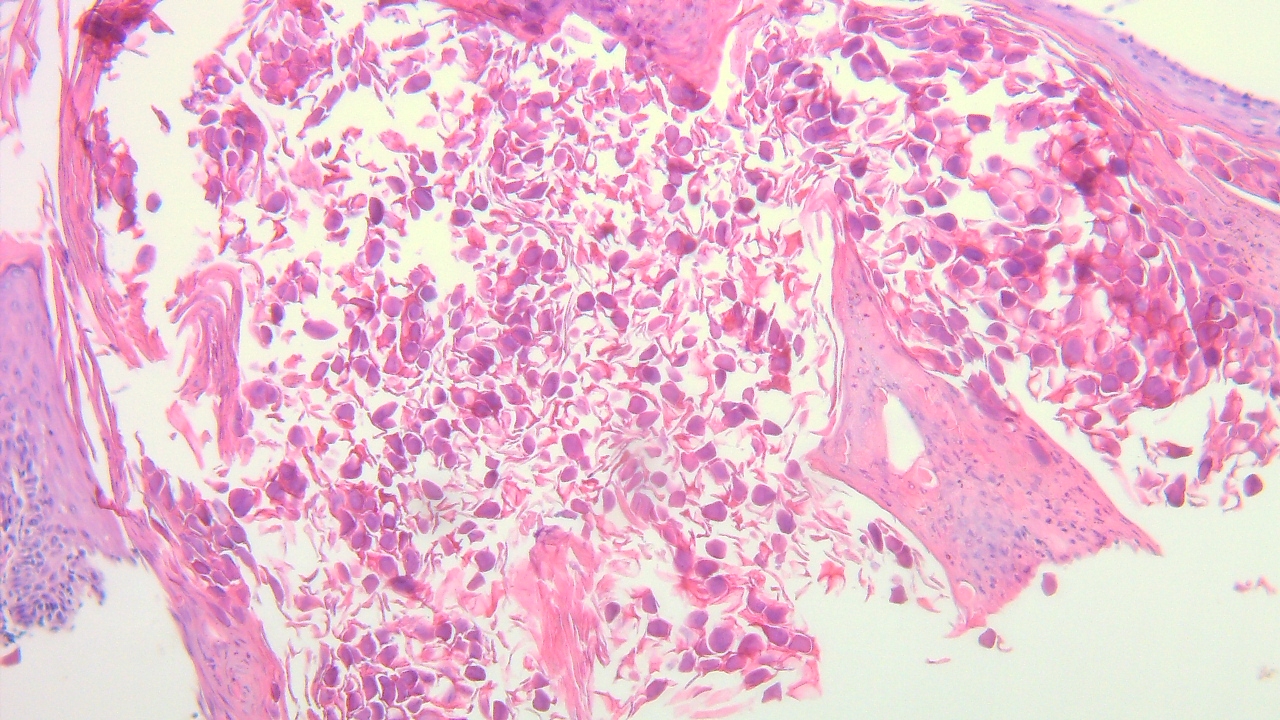

F, 11, lesion on the left lateral brow. DDx: Nevus, JXG, Calcinosis cutis, shave biopsy